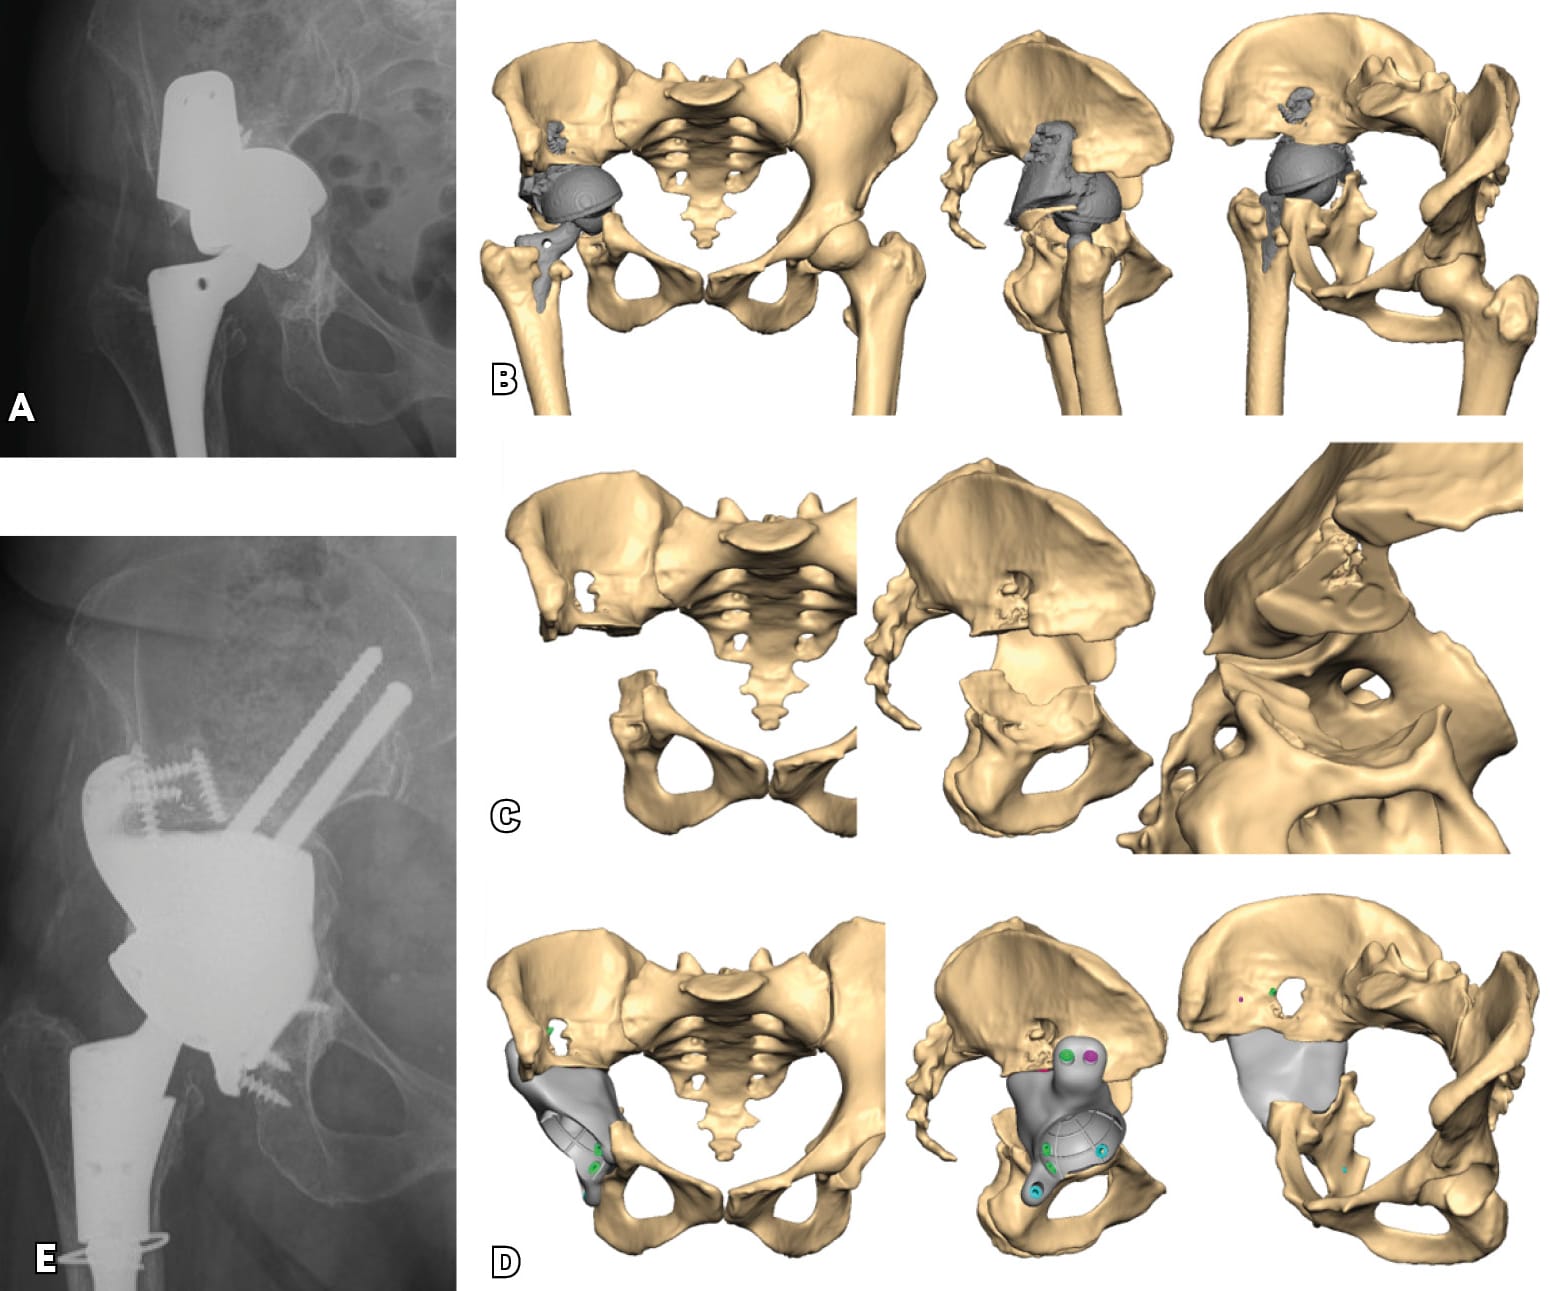

Severe post-operative defects. Principles of management and outcomes of specific patterns are not clearly reported in the literature. Based on the Sen clacification,[1] Sen RK, Mukhopadhyay R, Pattanshetti V, Saini G, Tripathy SK, Sethy SS, Sharma SK. A New Classification System for Acetabular Bone Defect Evaluation in Posttraumatic Acetabular Nonunion and Malunion. Indian J Orthop. 2022 Jun 27;56(9):1601-1612 types 1, 2, 3-A and 5 can be treated with surgical techniques used in revision THA surgery. For severe defects (such as 3-B, 4-A and 4-B), the restoration of hip center of rotation, cup offset, inclination and anterversion and hip stability can be achived only with custom-made implants (Figures 3 and 4).

Triflange and tumour like custom made acetabular impants. Modern technology allows the production of personalised implants for special conditions. These type of implants are custom made, porous coated titanium implants and are considered the last therapeutic salvage option, before excisional arthroplasty, for severe acetabular defects and PD. The implants are designed and manufactured based on pelvic models created by thin-slice pelvic 3-D CT-scans with metal subtraction software (Figures 7 and 8). Early and mid-term outcomes are encouraging but premium cost and length of production time limit their use.[20], DeBoer DK, Christie MJ, Brinson MF, Morrison JC. Revision total hip arthroplasty for pelvic discontinuity. J Bone Joint Surg Am. 2007; 89(4):870-876.[21], Taunton MJ, Ferhing TK, Edwards P, Bersasek T, Holt GE, Christie MJ. Pelvic discontinuity treated with custom triflange component: a reliable option. Clin Orthop Relat res. 2012; 470(2):428-434.[22] Zhang Y, Gao Z, Zhang B, Du Y, Ma H, Tang Y, Liu Y, Zhou Y. The application of custom-made 3D-printed titanium augments designed through surgical simulation for severe bone defects in complex revision total hip arthroplasty. J Orthop Traumatol. 2022; 6:23(1):37.

Concerns for the use of custom made implants are related to the accuracy of the image based technique used for their production, the accuracy of the implant 3D fitting and implantation, the appropriate surgical approach and exposure and the manufacturing and biology of the implant-bone interface.[23], Hothi H, Henckel J, Bergiers S, Di Laura A, Schlueter-Brust K, Hart A. The analysis of defects in custom 3D-printed acetabular cups: A comparative study of commercially available implants from six manufacturers. J Orthop Res. 2023; 41(7):1505-1516.[24], Di Laura A, Henckel J, Wescott R, Hothi H, Hart AJ. The effect of metal artefact on the design of custom 3D printed acetabular implants. 3D Print Med. 2020; 26:6(1):23. [25] Gruber MS, Jesenko M, Burghuber J, Hochreiter J, Ritschl P, Ortmaier R. Functional and radiological outcomes after treatment with custom-made acetabular components in patients with Paprosky type 3 acetabular defects: short-term results. BMC Musculoskelet Disord. 2020; 10:21(1):835.